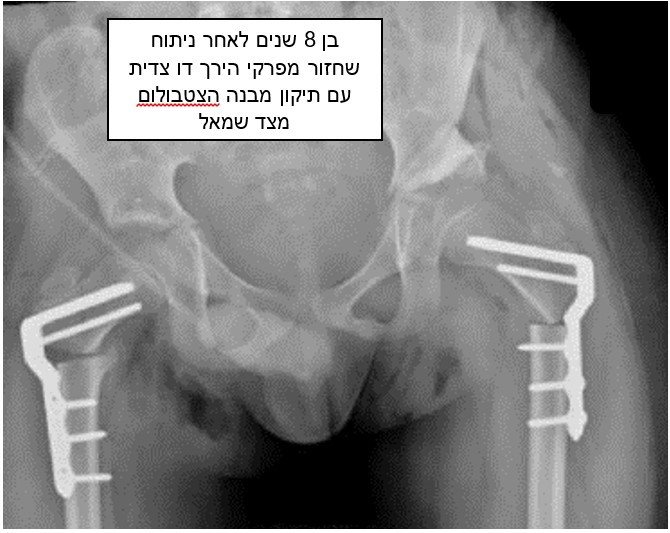

צילום נוסף של ילד אחר לאחר ניתוח שחזור מפרקי הירך ותיקון האצטבולום (מכתש) משמאל.

(ההסתכלות על צילומים נעשית כאלו הילד עומד מולנו).